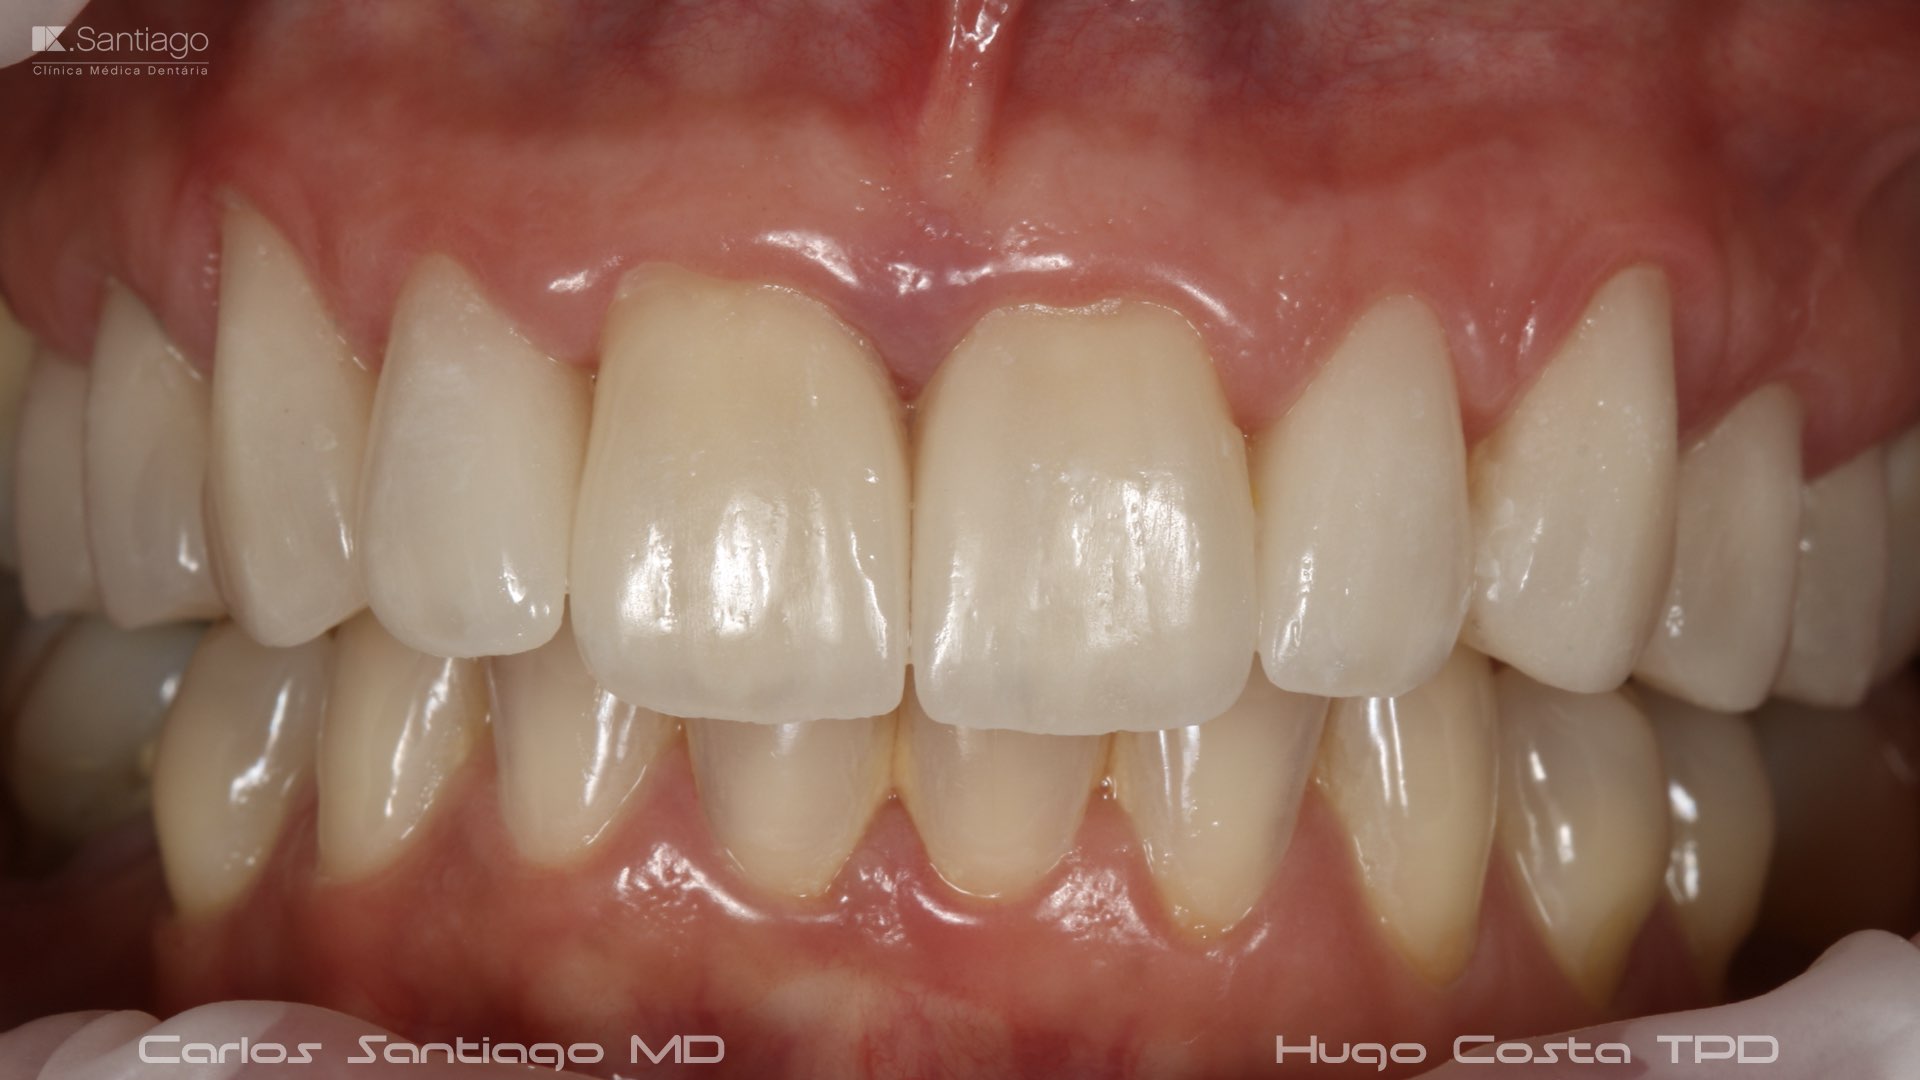

As Facetas Cerâmicas (lentes de contacto dentárias ou laminados), permitem corrigir da maneira mais estética e conservadora possível, problemas de forma e tamanho, côr e posição dos dentes, bem como substituir restaurações antigas e inestéticas.

São aderidas químicamente ao esmalte dentário de uma forma permanente, com o objectivo de melhorar a estética dos nossos pacientes.